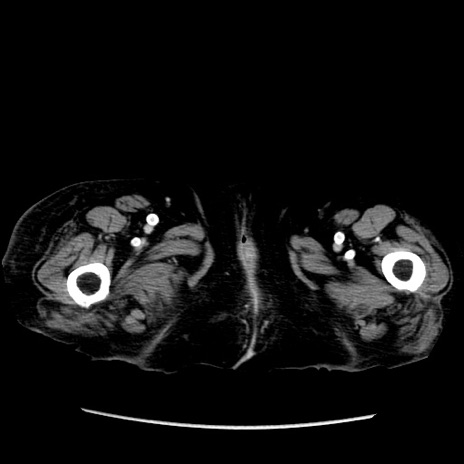

症例

冠状断像